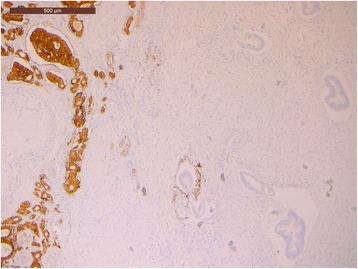

A 69-year-old woman was hospitalized in May 2016 for epigastric pain and weight loss. Her past medical history revealed an undefined main pancreatic duct dilation that was subsequently confirmed at CT scan (23 mm) and endoscopic ultrasound. There was no evidence of pancreatic masses, but the cephalic portion of the main pancreatic duct presented hypoechoic nodules. A diagnosis of the main-duct intraductal papillary mucinous neoplasm was made, and the patient underwent total pancreatectomy. Pathological examination showed a collision tumor constituted by a ductal adenocarcinoma involving the whole pancreas and a neuroendocrine tumor located in the duodenal peripancreatic wall and the head of the pancreas. There was one peripancreatic lymph node metastasis from the ductal adenocarcinoma and eight node metastases from the neuroendocrine tumor. These findings suggested a diagnosis of collision of neuroendocrine and ductal adenocarcinomas of the pancreas. The postoperative course was uneventful.

一名69岁女性于2016年5月因上腹部疼痛和体重减轻入院。她的既往病史显示有未明确的主胰管扩张,随后CT扫描(23毫米)和内镜超声证实了这一情况。没有胰腺肿块的证据,但主胰管头部出现低回声结节。诊断为主胰管内乳头状黏液性肿瘤,患者接受了全胰切除术。病理检查显示为碰撞瘤,由累及整个胰腺的导管腺癌和位于十二指肠胰周壁及胰头的神经内分泌肿瘤组成。导管腺癌有1个胰周淋巴结转移,神经内分泌肿瘤有8个淋巴结转移。这些发现提示胰腺神经内分泌癌与导管腺癌碰撞的诊断。术后过程顺利。